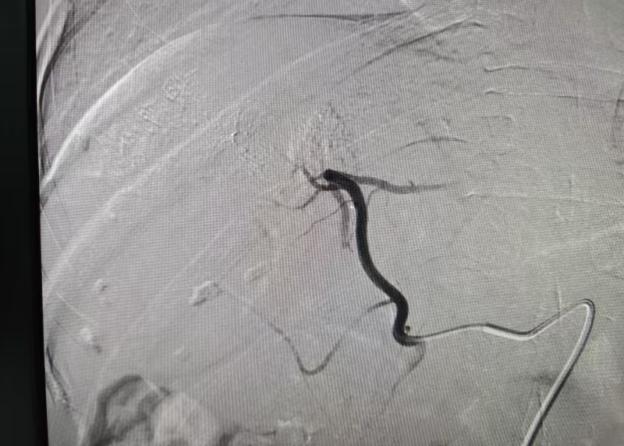

2025年2月20日按照治疗计划,王瑞涛副主任医师行精细化经导管肝动脉化疗药物灌注栓塞术(TACE),术中彻底栓塞肿瘤供血分支动脉,并注入碘化油及化疗药物杀灭肿瘤,术后患者耐受尚可,肝功轻微波动。TACE术后12天(2025年3月5日)经过术前评估,张晓刚主任医师行腹腔镜门静脉右支结扎+放射性粒子植入术,进一步控制肿瘤同时促进肝左叶增大,TACE术后17天(2025年3月10日)开始给予口服靶向药(仑伐替尼)联合免疫治疗(普特利单抗)。

经过三位重建,评估肿瘤体积缩小,肝左叶体积增大,全身PET-CT评估门脉癌栓没有活性,与家属充分沟通病情后决定行手术切除。